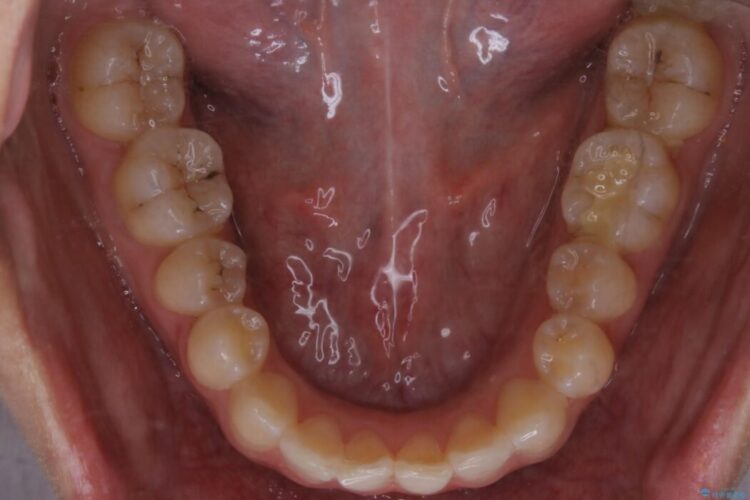

上顎歯列のガタガタを改善したいとのことで来院されました。

前歯の一部に反対咬合が見られ歯列がガタガタしていたためインビザラインでの矯正治療をご提案しました。